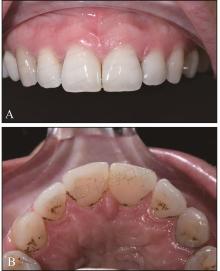

图 1

术前微笑及口内像A:微笑像;B:右侧位咬合像;C:正面咬合像;D:左侧位咬合像;E:上牙弓咬合面像;F:下牙弓咬合面像。"